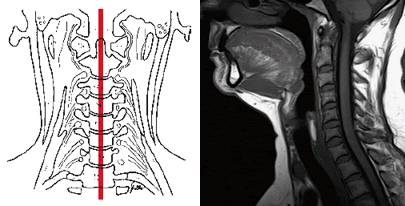

Виллизиев круг является ключевым элементом для нормального кровоснабжения всех систем нашего организма. Он образуется крупными позвоночными артериями, которые делятся на левую и правую ветви. В нормальных условиях развитие этих артерий происходит равномерно. Подключичная артерия, направляясь к черепной полости, разветвляется на входе.

Серьёзные изменения затрагивают область костного канала и артерии, которая в него впадает. При гипоплазии ткани головного мозга получают значительно меньше крови, что может привести к негативным последствиям.

Диагностика

Ранняя диагностика гипоплазии представляет собой серьезную задачу. Если у вас возникли подозрения на это заболевание, важно как можно скорее обратиться к невропатологу. Специалист проведет осмотр, выслушает ваши жалобы и назначит необходимые инструментальные исследования, такие как УЗИ позвоночных артерий.

Существует три основных метода диагностики гипоплазии:

-

УЗИ сосудов головы и шеи. Основное внимание уделяется дуплексному ангиосканированию, которое позволяет получить изображение артерии и оценить характеристики кровотока, включая его интенсивность, тип и диаметр. Этот метод безопасен и не представляет угрозы для здоровья пациента.

-

Томография шейной и головной области с контрастным усилением. Исследование проводится с использованием магнитно-резонансных и компьютерных томографов, при этом сосуды заполняются контрастными веществами для более детального анализа.

-

Ангиография. Этот метод позволяет графически зафиксировать особенности расположения, анатомическую структуру и соединения сосудистых образований. С помощью рентгеновского оборудования можно оценить состояние позвоночной артерии, заполнив её контрастным веществом. Изображение выводится на экран, а для введения контраста производится пункция крупной артерии на одной из конечностей.